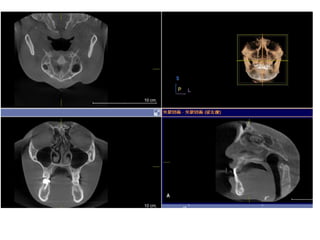

790516

810410

蕭郁庭